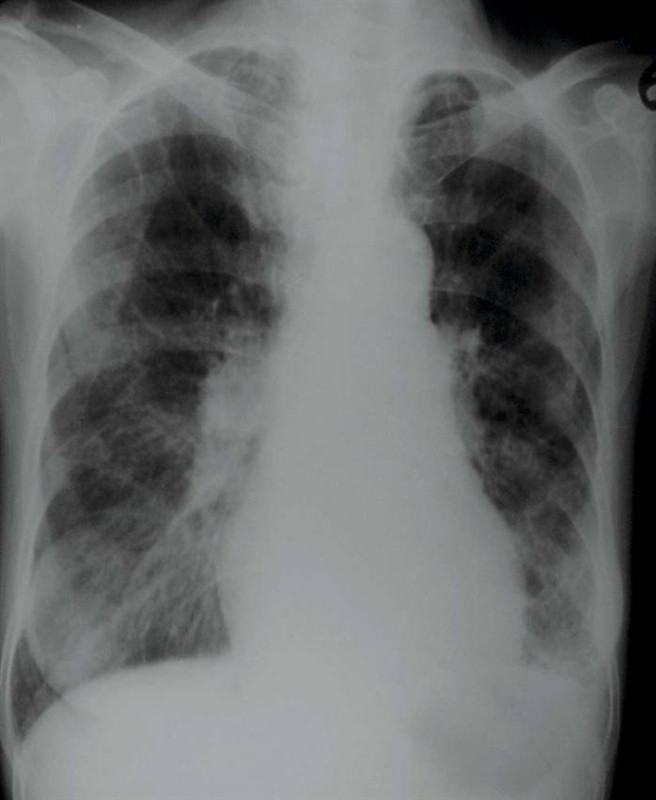

照片名称:肺炎—右肺支气管扩张